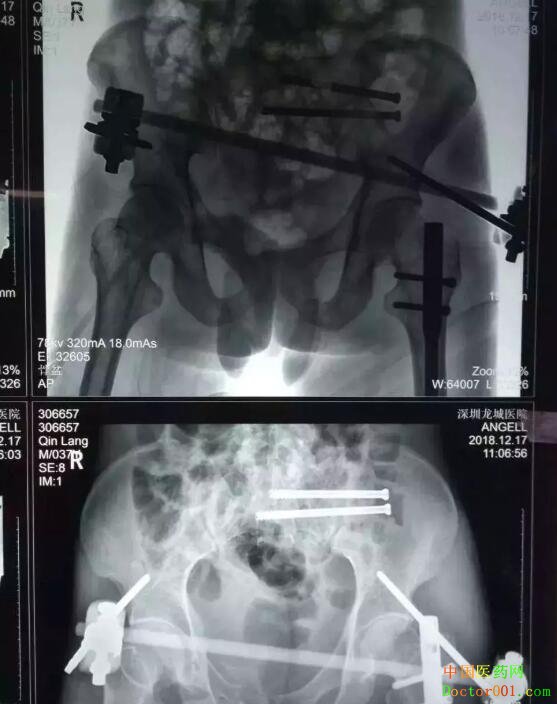

覃先生:“当时完全懵了,只感到下身剧烈疼痛,全身发冷,有一种死亡来临的感觉。” 覃先生回忆说,住进医院后自己翻身都不行,只是感觉到全身都痛,难以忍受。 由于覃先生病情非常危重,医院立即开启绿色通道,紧急安排住进骨科抢救室。根据检查结果初步诊断覃先生为重症多发伤。骨科博士汪金平详细介绍说,患者的主要诊断包括:① 创伤性休克;② 骨盆多发不稳定骨折:左侧骶骨粉碎性骨折、右侧耻骨上下支粉碎性骨折;③ 左侧股骨干骨折;④ 右侧踝关节骨折;⑤ 急性失血性贫血等情况。

“这是一个很棘手的病例。”主治医生介绍,虽然经过及时的专业救治和护理,覃先生的病情日趋稳定,但患者系非常严重的不稳定型骨盆骨折,合并这种骨折的患者,受伤时伤力都非常大,受伤部位也比较多,所以病情都比较复杂而严重。 由于骨盆骨折极度不稳定,断骨需要快速生长骨痂,所以骨盆骨折的最佳手术时机是伤后一周内,否则将无法闭合复位骨折及无法实施创伤最小的经皮内固定术,最终的治疗效果可能比较差,主治医生分析说。 由于患者情况比较复杂,主治医生申请全院多学科专家会诊,详细分析患者病情,进一步评估手术风险,专家组讨论认为,患者系全身多处骨折,并且损伤严重,合并严重的全身性炎症反应,争取全身骨折用一次手术就全部做好,但长时间的麻醉会影响手术后肺功能的恢复,因此,要将手术的损伤降低到最小,同时要在最短的时间内完成手术。 影像资料显示,患者骶1椎存在发育畸形,这种骶骨畸形增加了实施骶髂螺钉固定的风险,因为骶骨里和周围有大量的神经和血管呈网状分布,手术中一点偏差可能造成无法挽回的严重后果,轻者损伤神经造成患者瘸腿,重者损伤血管导致大出血而造成患者死亡。 经过慎密的研究,专家组认为患者身体条件不适合实施传统的切开复位固定术,实施微创固定术对患者是最佳治疗选择。

12月14日,在患者伤后第三天,由博士带领团队为患者施行了透视下实施经皮骶髂螺钉固定术,首先闭合复位骨盆骨折成功,即刻经皮置钉完成前环外固定架固定术以稳定骨盆。然后顺利地经骶1椎和骶2椎各置入一枚骶髂螺钉固定,至此骨盆的前后环均获得牢固固定。手术历时近2小时,所有切口加起来的总长度不超过5cm,手术中出血不到10毫升。术后复查显示骨折复位和内固定位置都很好,医生评估预计手术后三个月可以正常行走。 覃先生 : “手术完,几乎没有感觉到痛苦,术后当天,已经可以背靠在床上坐起来吃饭了。”“汪医生水平很高,人也很好。”